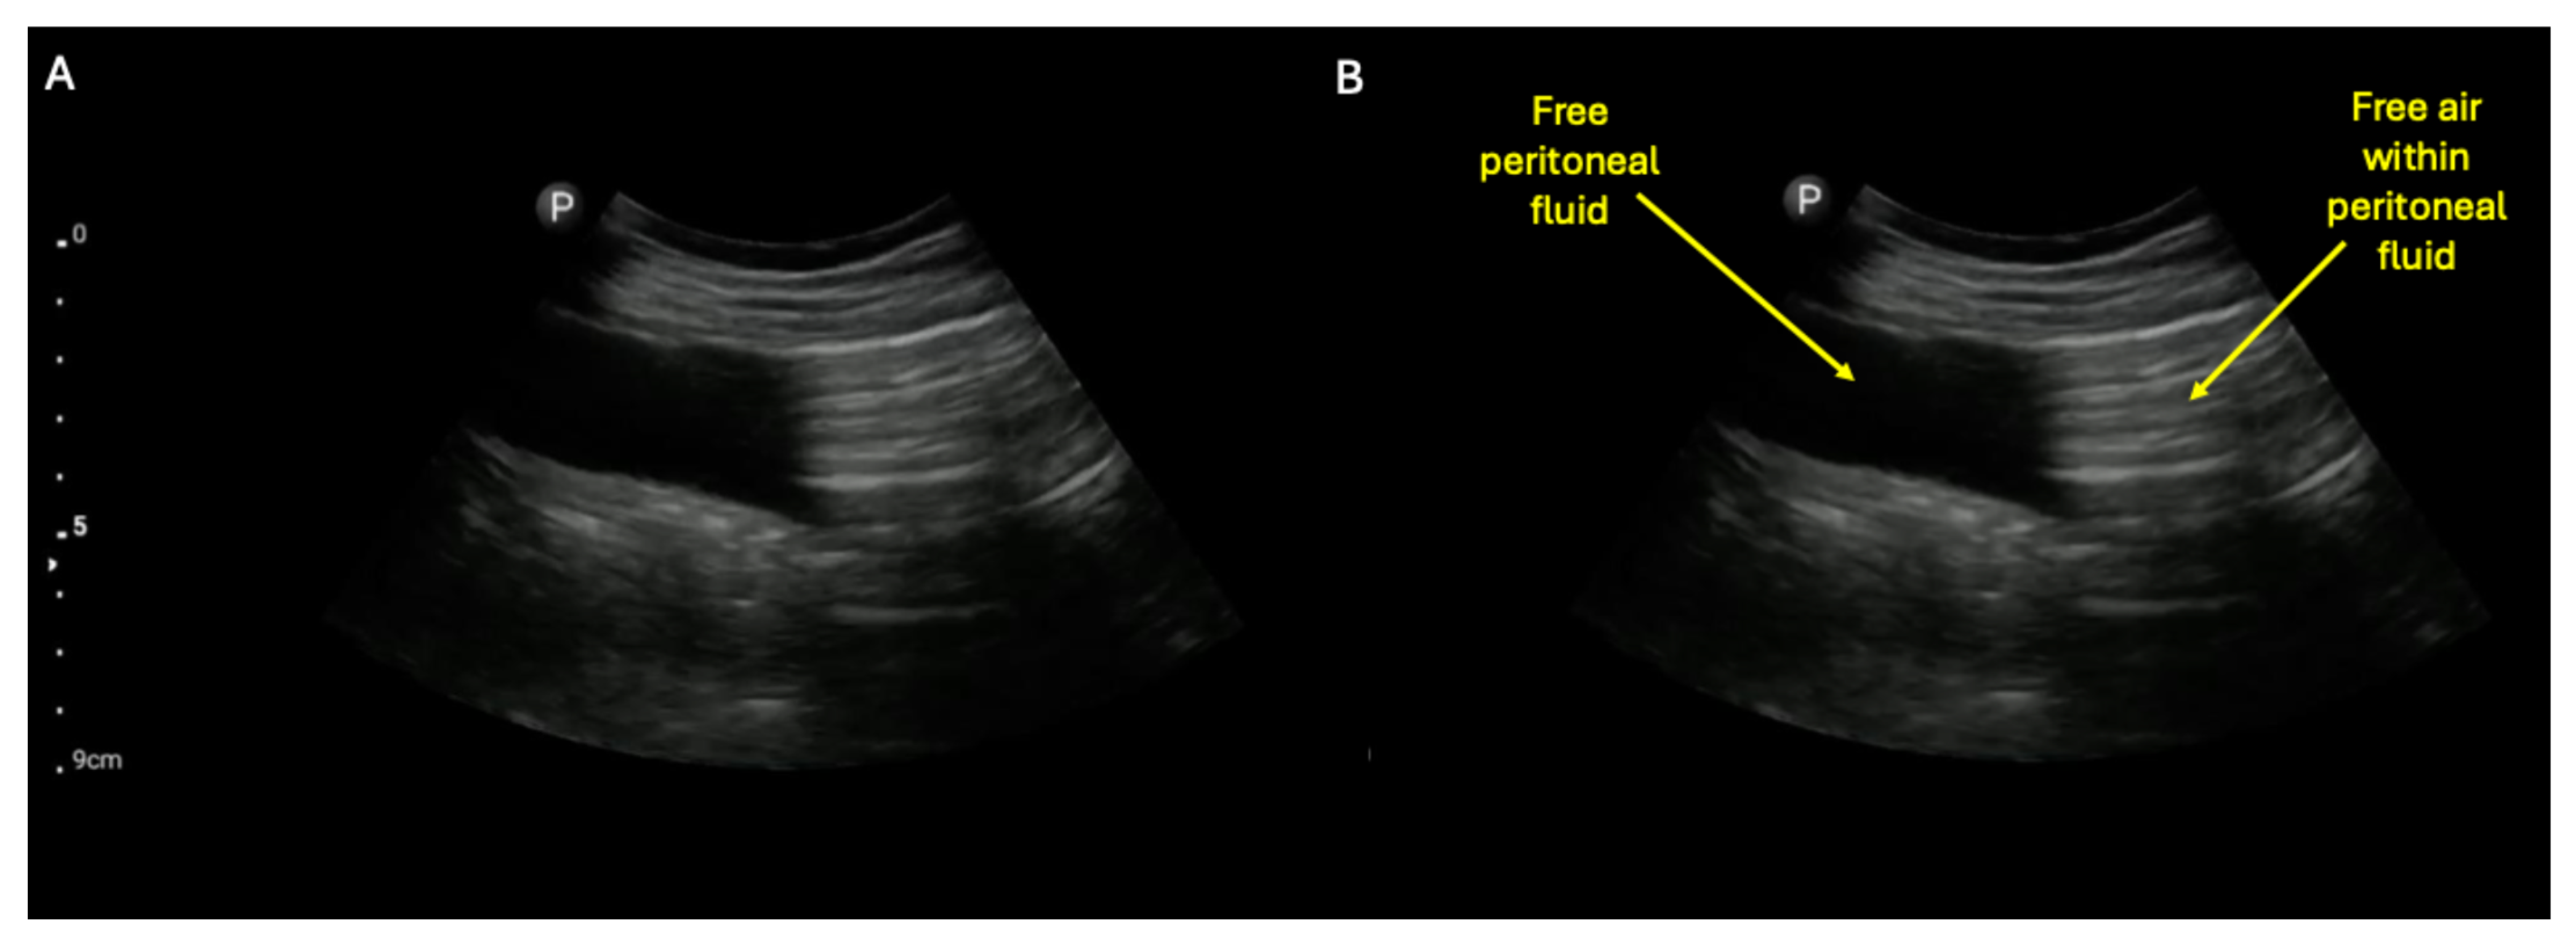

- Khor, M.; Cutten, J.; Lim, J.; Weerakkody, Y. Sonographic detection of pneumoperitoneum. BJR Case Rep. 2017, 3, 20160146. [Google Scholar] [CrossRef] [PubMed]

- Jiang, L.; Wu, J.; Feng, X. The value of ultrasound in diagnosis of pneumoperitoneum in emergent or critical conditions: A meta-analysis. Hong Kong J. Emerg. Med. 2019, 26, 111–117. [Google Scholar] [CrossRef]